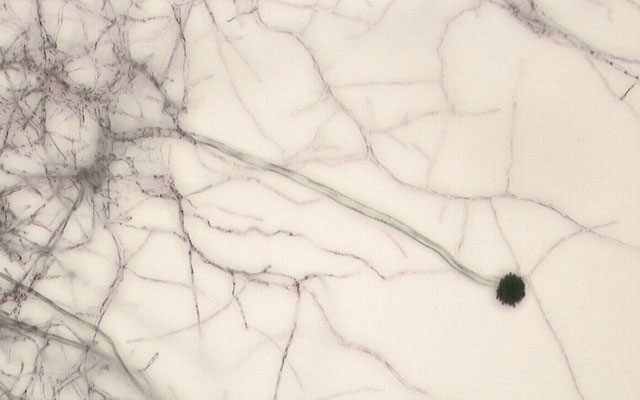

Every day, people unknowingly inhale hundreds of invisible fungal spores. Most pass through harmlessly. But some—like the Aspergillus fungus—are becoming increasingly dangerous. Once a quiet recycler of nature’s debris, it is now mutating into a global health threat that can eat humans from the inside out.

Three main strains—Aspergillus flavus, A. fumigatus, and A. niger—are leading this fungal onslaught. These moulds thrive in soil, on grains, and even animal feathers. Their spores can infect lungs, rot crops, and contaminate food all at once. In people with weakened immune systems, especially hospital patients, they cause life-threatening infections. But even the healthy may soon be at risk.